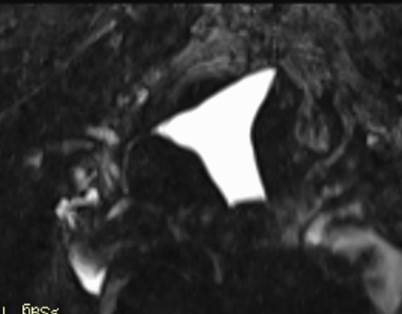

Разработка и внедрение новой методики магнитно-резонансной гистеросальпингографии при бесплодии. Руководитель: Труфанов Г.Е.

Результаты: У женщин с бесплодием выявлены структурные изменения органов малого таза, которые могут быть причиной бесплодия или фоном, на котором развивается бесплодие. МРТ-семиотика визуализируемой патологии характеризуется наличием у женщин аномалий развития, доброкачественных образований матки и придатков, различных форм эндометриоза.

1. Разработаны, усовершенствованы и внедрены для клинического применения ряд методик и устройств – алгоритм МР-гистеросальпингографии для диагностики бесплодия у женщин репродуктивного возраста путем одномоментного выполнения комплексного МР-исследования.

Актуальность этой разработки обусловлена трудностями визуализации морфологических и функциональных изменений органов малого таза у женщин репродуктивного возраста при бесплодии, что важно для выбора тактики ведения и лечения пациенток.

Комплексное МРТ исследование органов малого таза у женщин репродуктивного возраста позволяетдетализированно охарактеризовать выявленные изменения — как морфологические, так и функциональные.

Проведение МРТ с введением контрастного вещества в полость матки (МР-ГСГ) позволяет оценить контуры полости матки, форму матки, визуализировать очертания рогов матки, интрамуральную, истмическую и ампулярную части маточных труб, степень проникновения контрастного препарата в брюшную полость и проходимость маточных труб.

Левая маточная труба не проходима в интрамуральном отделе (стрелка), правая маточная труба проходима на всем протяжении (пунктирная стрелка).